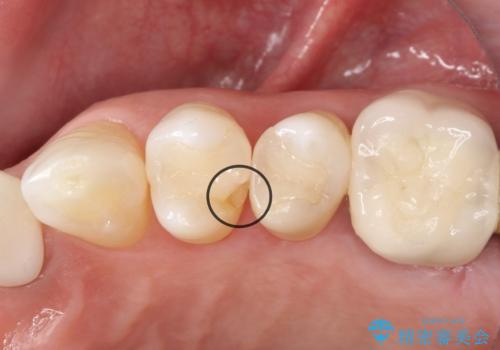

【セラミックインレー】被せ物が欠けた

- 奥歯の被せ物が欠けたを主訴に来院された患者様です。欠けてしまった被せ物を除去後セラミックインレーで治療を行いました。

欠けた範囲が大きく被せ物を外して後、セラミックインレーで治療を行いました。欠けたままの状態を放置しているとそこに食べ物が詰まり虫歯になってしまうので早めの治療が必要です。